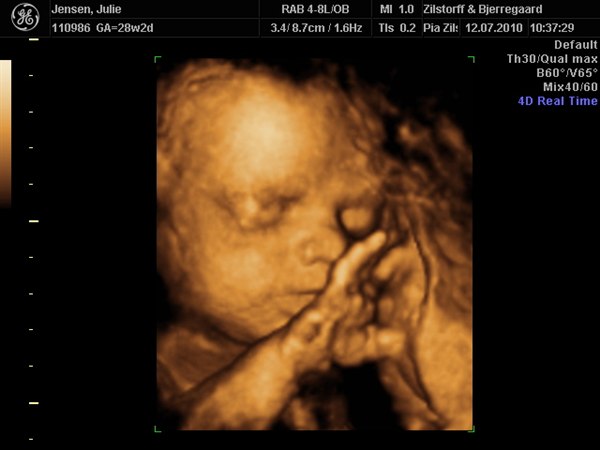

smilehuller og ligner helt sikkert Viktor

Hun skulle bestemt ikke snydes for noget så hun kiggede rigtig med da hun blev scannet og vinkede meget ivrigt til sin storebror som ikke kunne få øjne fra tvet og blev helt sat i putte mode da scanningsjordmoderen lod os høre hjertelyd hele 4 gange...

Kan slet ikke komme mig over hvor fantastisk det er at se det lille menneske inden i en

Vedhæftede fotos (klik for at se i fuld størrelse)